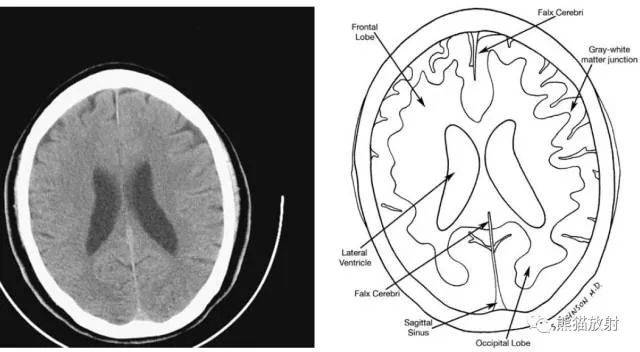

3、正常解剖:

从前至后:大脑镰、额叶、灰白质交界处、侧脑室、大脑镰、枕叶、矢状窦。